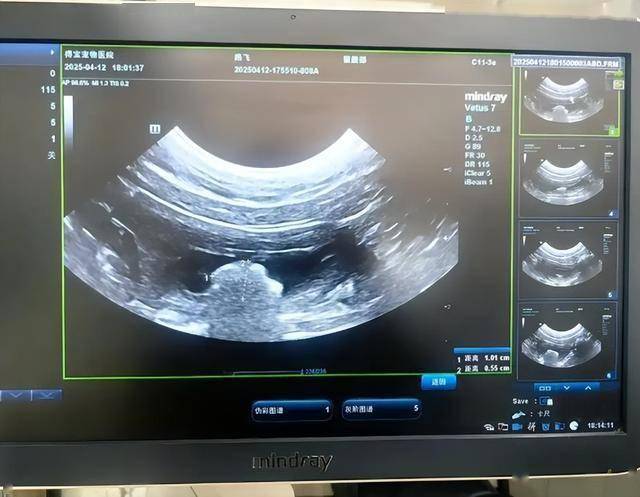

轻度黄疸有时不太明显,但在自然光下对比过去照片,往往能发现变化。黄疸是肝胆问题的重要信号之一,出现后不要观望,尽快到医院完善肝功能、乙肝两对半、腹部彩超等检查。